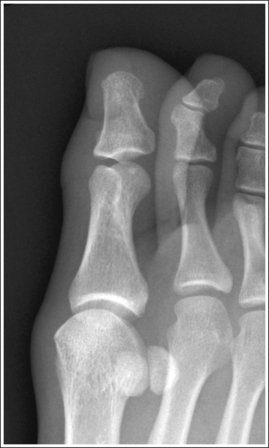

See Figure 6-12 and Box 6-5.

The foot demonstrates an AP projection. The joint space between the medial (first) and intermediate (second) cuneiforms is open, approximately 0.75 inch (2 cm) of the calcaneus is demonstrated without talar superimposition, and concavity on both sides of the first metatarsal midshaft is equal.

• An AP projection of the foot is obtained by flexing the supine patient's knee and placing the plantar foot surface against the IR (Figure 6-14). The lower leg, ankle, and foot should remain aligned, and equal pressure should be applied across the plantar surface.